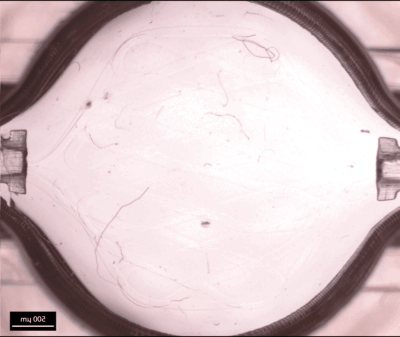

„Die Mikroblutgefäße in die Gewebestrukturen zu integrieren, ist bis heute eine große Herausforderung“, weiß Matthias Ryma. Doch der Biologe kann helfen. Im Rahmen seiner mehrfach ausgezeichneten Doktorarbeit am Institut für Funktionsmaterialien und Biofabrikation des Universitätsklinikums Würzburg (UKW) hat Matthias Ryma ein Verfahren entwickelt und zum Patent angemeldet, mit dem er in einem hochauflösenden 3D-Drucker filigrane Fasern aus einem speziellen Polymer herstellen kann. Dieser in der Produktion aufwändige Druck dient als winziges Gerüst, auf dem der Wissenschaftler im Labor naturgetreue Blutgefäßstrukturen herstellen kann. „Wir betten die Faser in eine Gewebestruktur ein und lösen diese dann durch Temperatureinstellungen auf, so dass nur noch ein Kanal übrig bleibt. Wir opfern sozusagen die Faser und erhalten ein biomimetisches Mikrokanal-Netzwerk, das natürlichen Blutgefäßen ähnelt“, so Ryma. Je nach Forschungsfokus kann dann eine Matrix mit den entsprechenden Zellen auf das vaskularisierte Gewebe gegeben werden; die Zellen teilen und verteilen sich, und durch die permanente Nährstoff- und Sauerstoffzufuhr kann das Gewebe wachsen und reifen.

https://doi.org/10.1002/adma.202200653 Vorhergehende Studie zur Nutzung thermoresponsiver Opferstrukturen zur Herstellung perfusionsfähiger Gewebe in Bioreaktoren: M. Ryma, H. Genç, A. Nadernezhad, I. Paulus, D. Schneidereit, O. Friedrich, K. Andelovic, S. Lyer, C. Alexiou, I. Cicha, J. Groll, A Print-and-Fuse Strategy for Sacrificial Filaments Enables Biomimetically Structured Perfusable Microvascular Networks with Functional Endothelium Inside 3D Hydrogels. Adv. Mater. 2022.